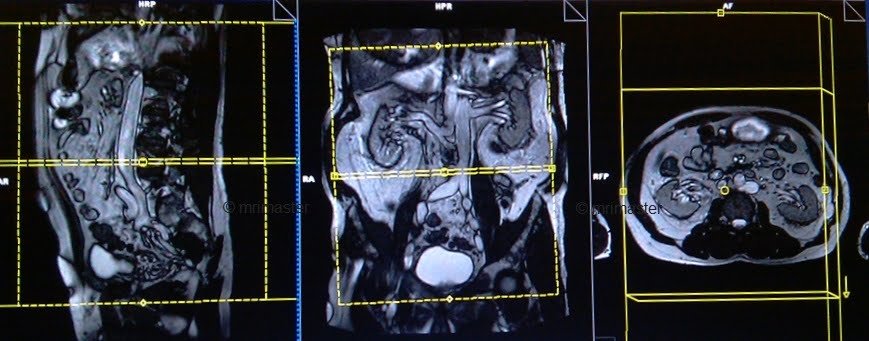

T2 HASTE\TRUFI axial 4 mm

Plan the axial slices on the coronal plane, angle the positioning block parallel to the right and left iliac crest. Check the positioning block in the other two planes. An appropriate angle must be given in the sagittal plane (horizontally across the abdomen). The slices must be sufficient to cover the entire abdomen and pelvis from the diaphragm down to the symphysis pubis. Use a field of view (FOV) that is large enough to encompass the entire abdomen, typically ranging from 350mm to 400mm.

Parameters

TR 4-5 | TE 2-3 | FLIP 60 | NEX 1 | SLICE 4 MM | MATRIX 320×256 | FOV 350-400 | PHASE R>L | OVERSAMPLE 50% | IPAT ON |